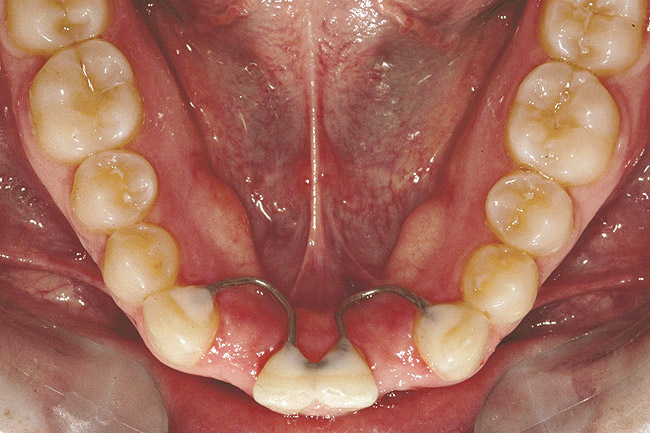

Fig 18 (through Fig 21). Note lack of alveolar development from congenitally missing Nos. 24 and 25. Surgical procedures after 5 months of orthodontic alignment included single-tooth osteotomies Nos. 6 to 11 and Nos. 21 to 28 and buccal corticotomies on all other teeth. Anchorage plate was stabilized to piriform rim.

Fig 20. Note lack of alveolar development from congenitally missing Nos. 24 and 25. Surgical procedures after 5 months of orthodontic alignment included single-tooth osteotomies Nos. 6 to 11 and Nos. 21 to 28 and buccal corticotomies on all other teeth. Anchorage plate was stabilized to piriform rim.

Fig 21 (and Fig 20). There is significant lateral dentoalveolar expansion of arches and alveoloskeletal correction in maxillary and mandibular anterior regions. Alveolar bone volume was increased in lower anterior to create optimal implant sites and establish ideal interincisal function and stability.